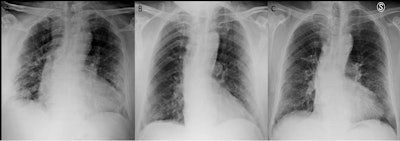

An example of a patient with a chest x-ray score of 6 at admission and scores of 4 before discharge and at three months follow-up. Image courtesy of Radiology.About half of patients (49.6%) had chest x-ray scores of 0, which indicated a complete radiological recovery three months after discharge. The other half (50.4%) had x-ray scores of 3 (+/- 2.6) at three months. In patients with higher scores at three months, age, the number of days of hospitalization and their chest x-ray scores at admission and before discharge were also statistically higher, the researchers found.